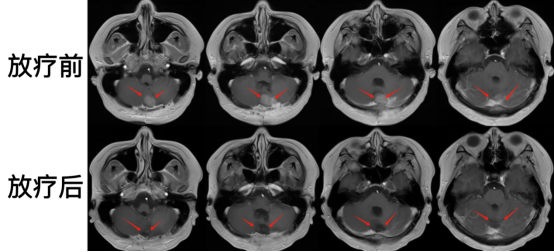

患者放射治療過(guò)程順利,除脫發(fā)外,無(wú)明顯不適及副反應(yīng)的發(fā)生。治療后復(fù)查磁共振,可見(jiàn)顱內(nèi)小腦殘留病灶完全消失,取得良好治療效果。

圖注:頭部磁共振,放療前,可見(jiàn)小腦殘留病灶,病灶明顯強(qiáng)化;放療后,顱內(nèi)腫瘤病灶完全消失。